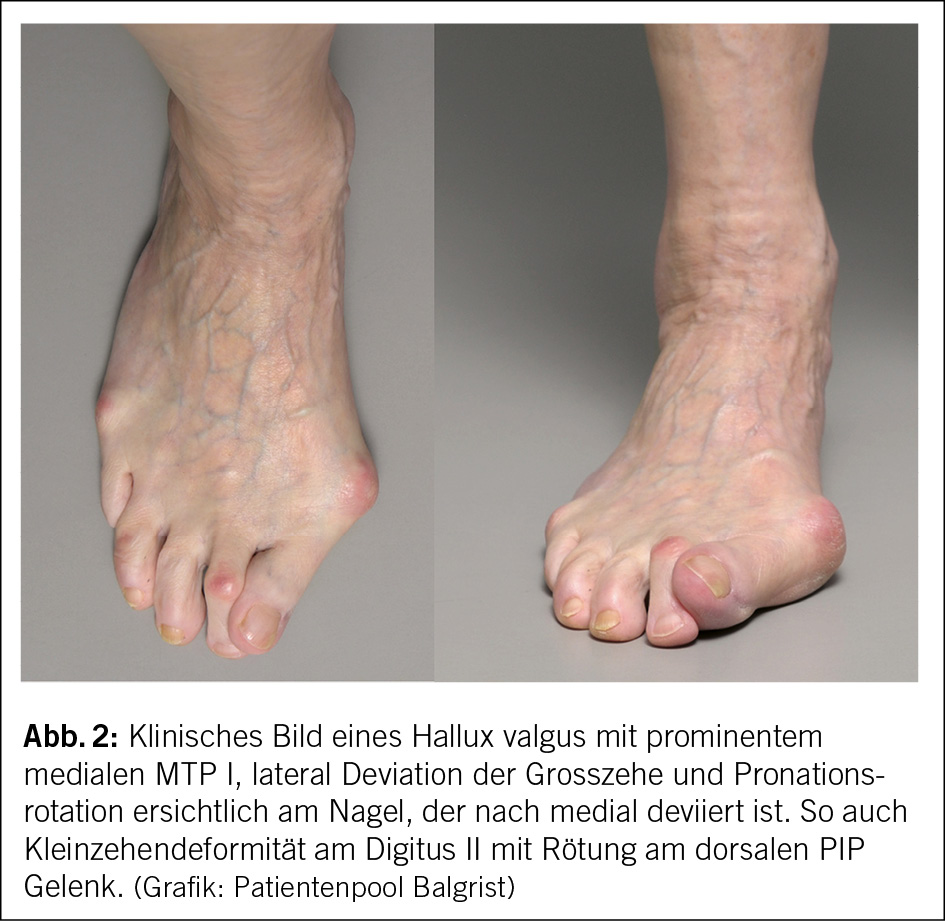

Meist präsentieren sich die Patienten mit einem schmerzhaften und prominenten medialen MTP I (Abb. 2). Dies führt oft zu Druckstellen mit Rötung und Schmerzen, so ist es in engem Schuhwerk schmerzhafter als in weiten und weichen Schuhen. Ist die Deformität fortgeschritten, kann es zu interdigitalen Konflikten kommen, mit Ulcerationen oder Kleinzehendeformitäten. Ebenso wird bei Rotation des ersten Strahls die mediale Seite des MTP vermehrt belastet, was medioplantar zu Hyperkeratosen führen kann. Bei äusserst ausgeprägten Befunden steht der zweite Strahl über oder unter dem ersten Strahl, hier spricht man von einer Superductussituation.